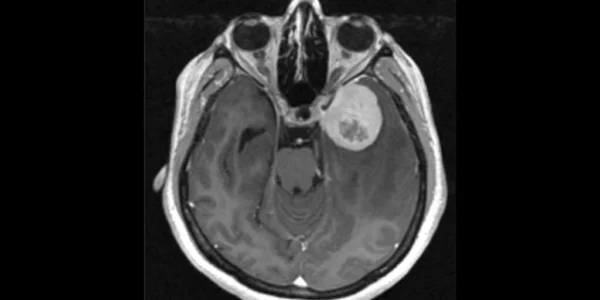

Studi Mayo Clinic: Gen TERT Dapat Jadi Alarm Dini Kekambuhan Tumor Otak Meningioma

Rochester, Minggu 23 November 2025- Sebuah studi multi-institusi yang dipimpin oleh Mayo Clinic menunjukkan temuan signifikan yang dapat mengubah cara dokter mendiagnosis dan menangani meningioma, jenis tumor otak yang paling umum Penelitian yang dipresentasikan pada konferensi Society for Neuro-Oncology (22/11) ini…